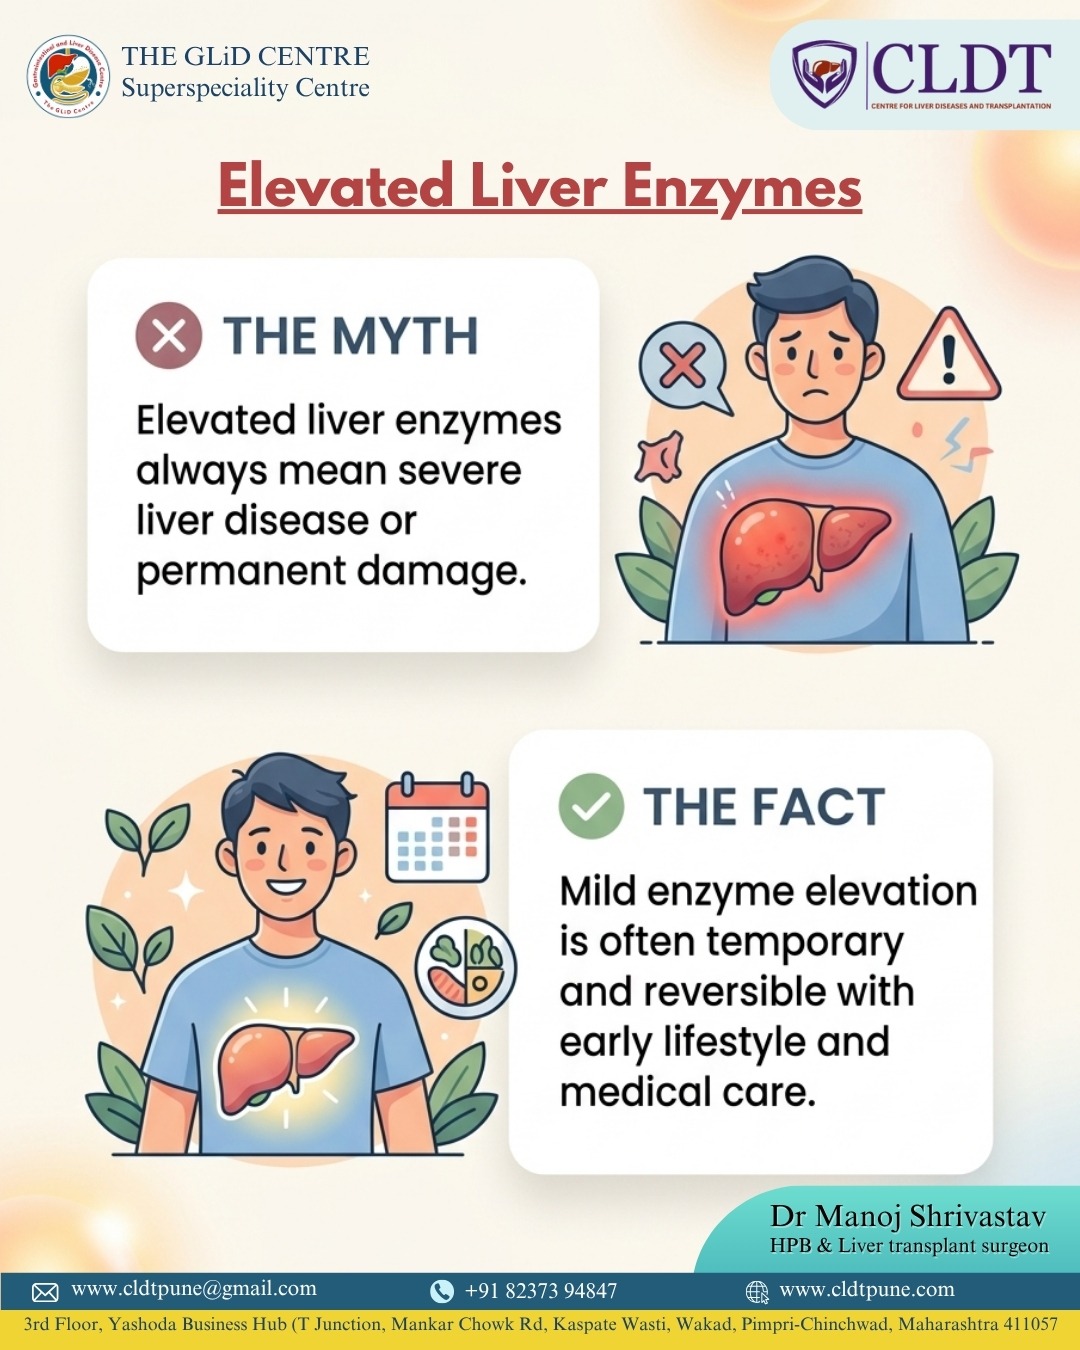

Healthy Foods for Your Liver: What to

Your liver plays a vital role in keeping your body...